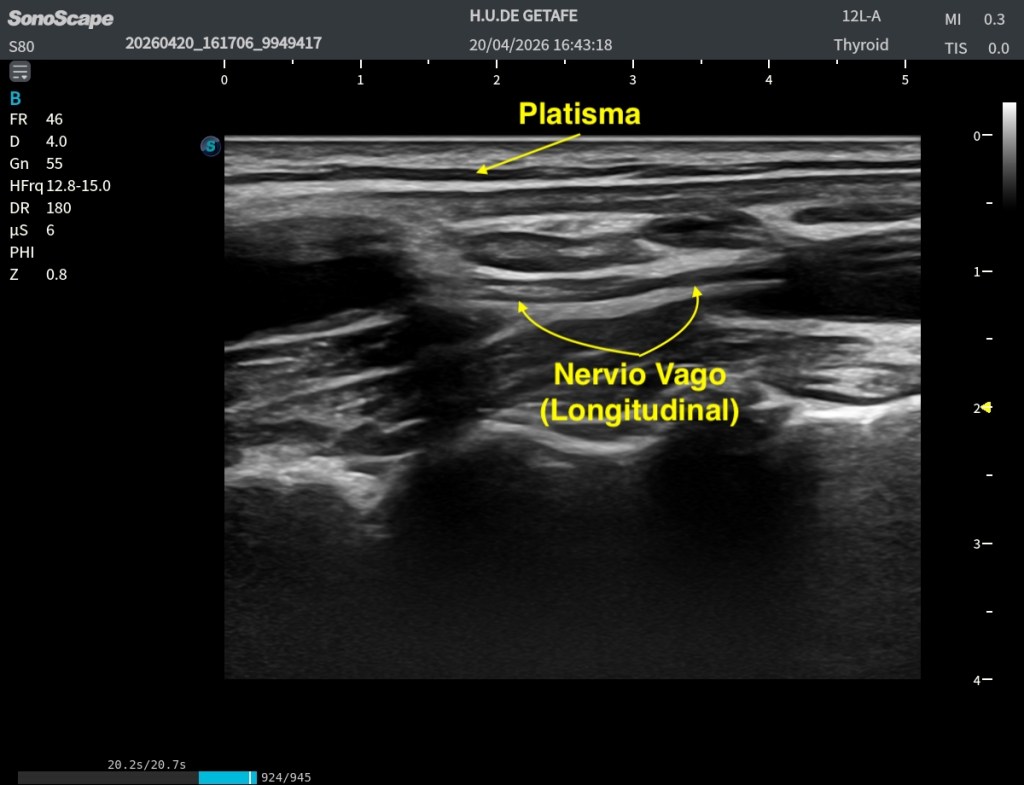

A partir de ese momento, sin perder la referencia, vamos a girar el transductor 90 grados hacia craneal. Con este movimiento conseguimos alinear el plano de corte con el eje del nervio, lo que nos permite obtener una visualización en eje longitudinal o sagital, confirmando su trayecto y morfología.